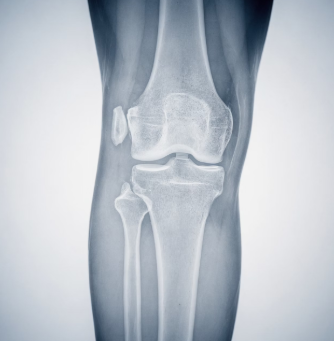

1. 퇴행성 관절염

중장년층에서 가장 흔한 원인입니다.

관절 연골이 닳으면서 염증이 생기고, 그 결과 관절액이 늘어나 무릎이 붓게 됩니다.

계단 오르내리기나 오래 걸을 때 통증이 동반되는 경우가 많습니다.